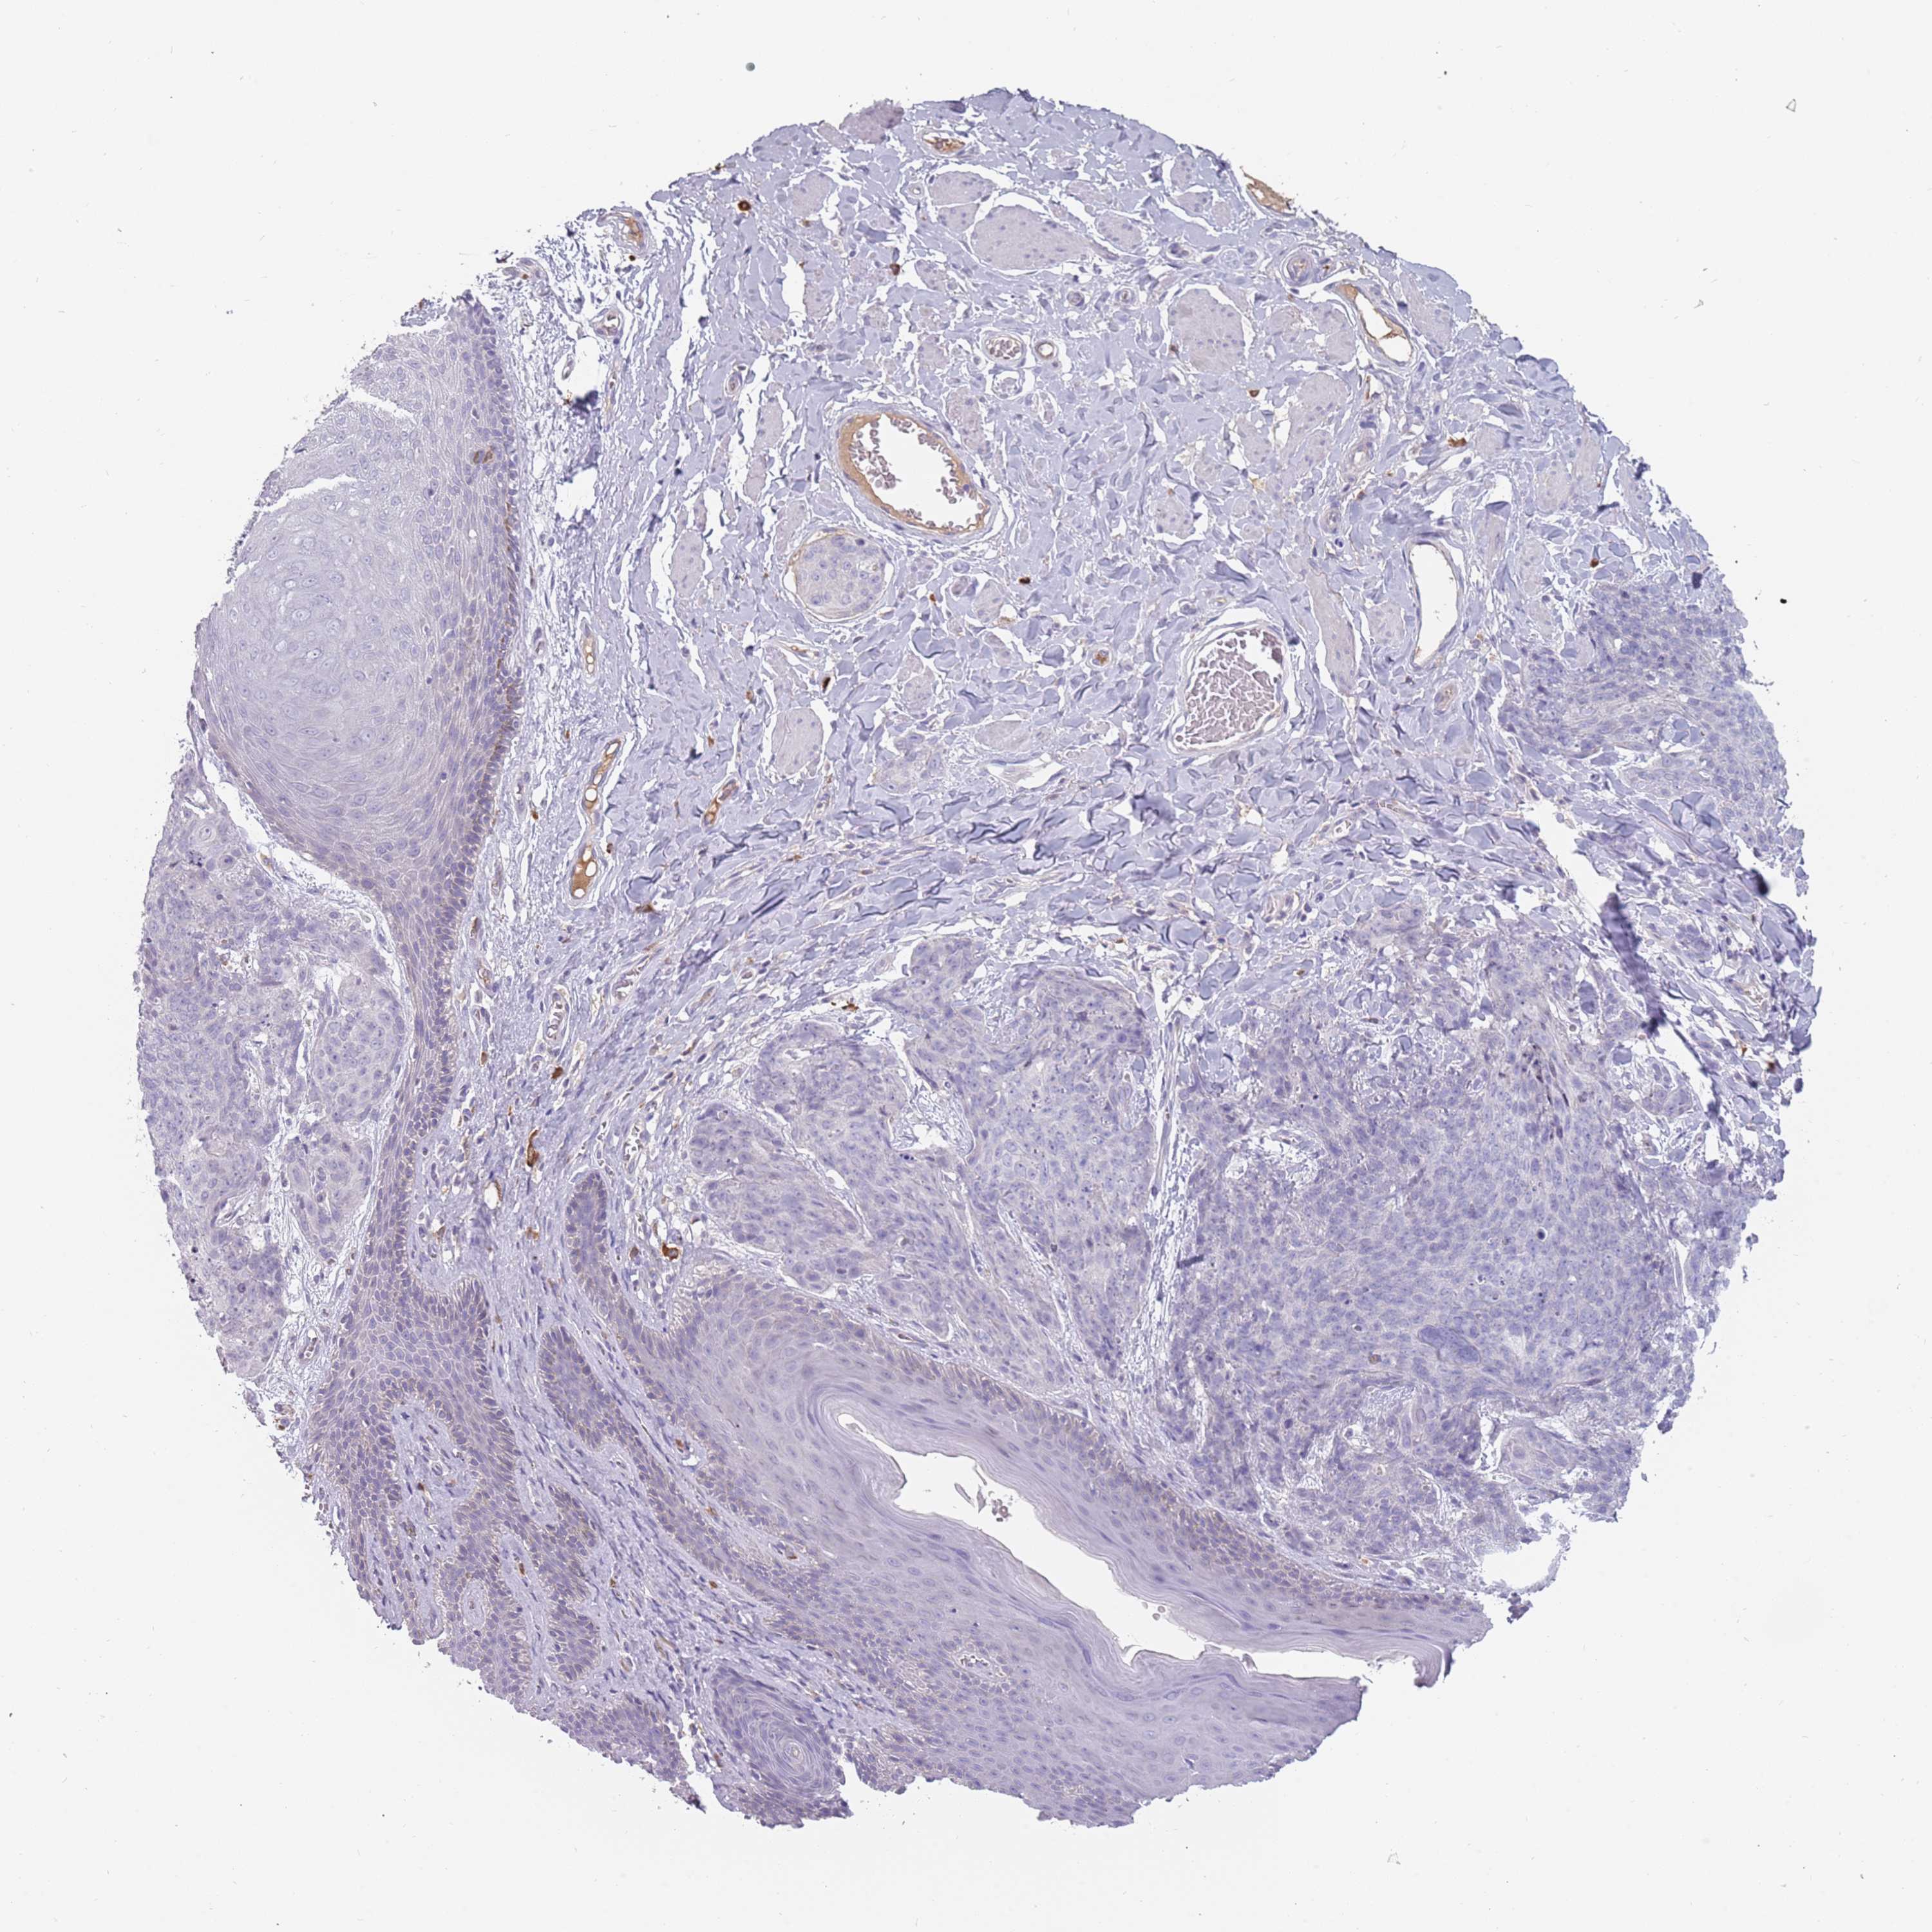

SKIN CANCER - Protein expressioni

A mouse-over function shows sample information and annotation data. Click on an image to view it in a full screen mode. Samples can be filtered based on level of antibody staining by selecting one or several of the following categories: high, medium, low and not detected. The assay and annotation is described here.

Antibody stainingi

Antibody staining in the annotated cell types in the current human tissue is reported as not detected, low, medium, or high, based on conventional immunohistochemistry profiling in selected tissues. This score is based on the combination of the staining intensity and fraction of stained cells.

Each image is clickable and will lead to virtual microscopy that enables deeper exploration of all samples and also displays staining intensity scores, fraction scores and subcellular localization as well as patient and tissue information for each sample.

Antibody HPA037763

Basal cell carcinoma